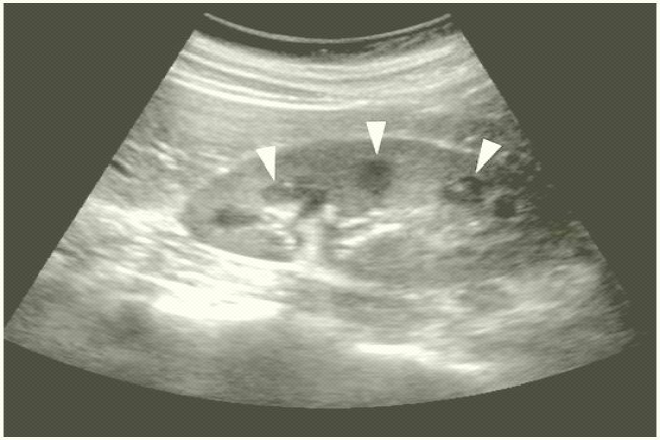

ANATOMÍA NORMAL RIÑÓN

• En el adulto, el riñón mide aproximadamente 11 cm de longitud, 2.5 cm de grosor y 5 cm de anchura, con un peso entre 120 y 170 gramos.

• El riñón izquierdo generalmente es más grande que el derecho.

• El riñón adulto normal tiene una forma de alubia con un contorno convexo liso y una estructura interna bien definida.